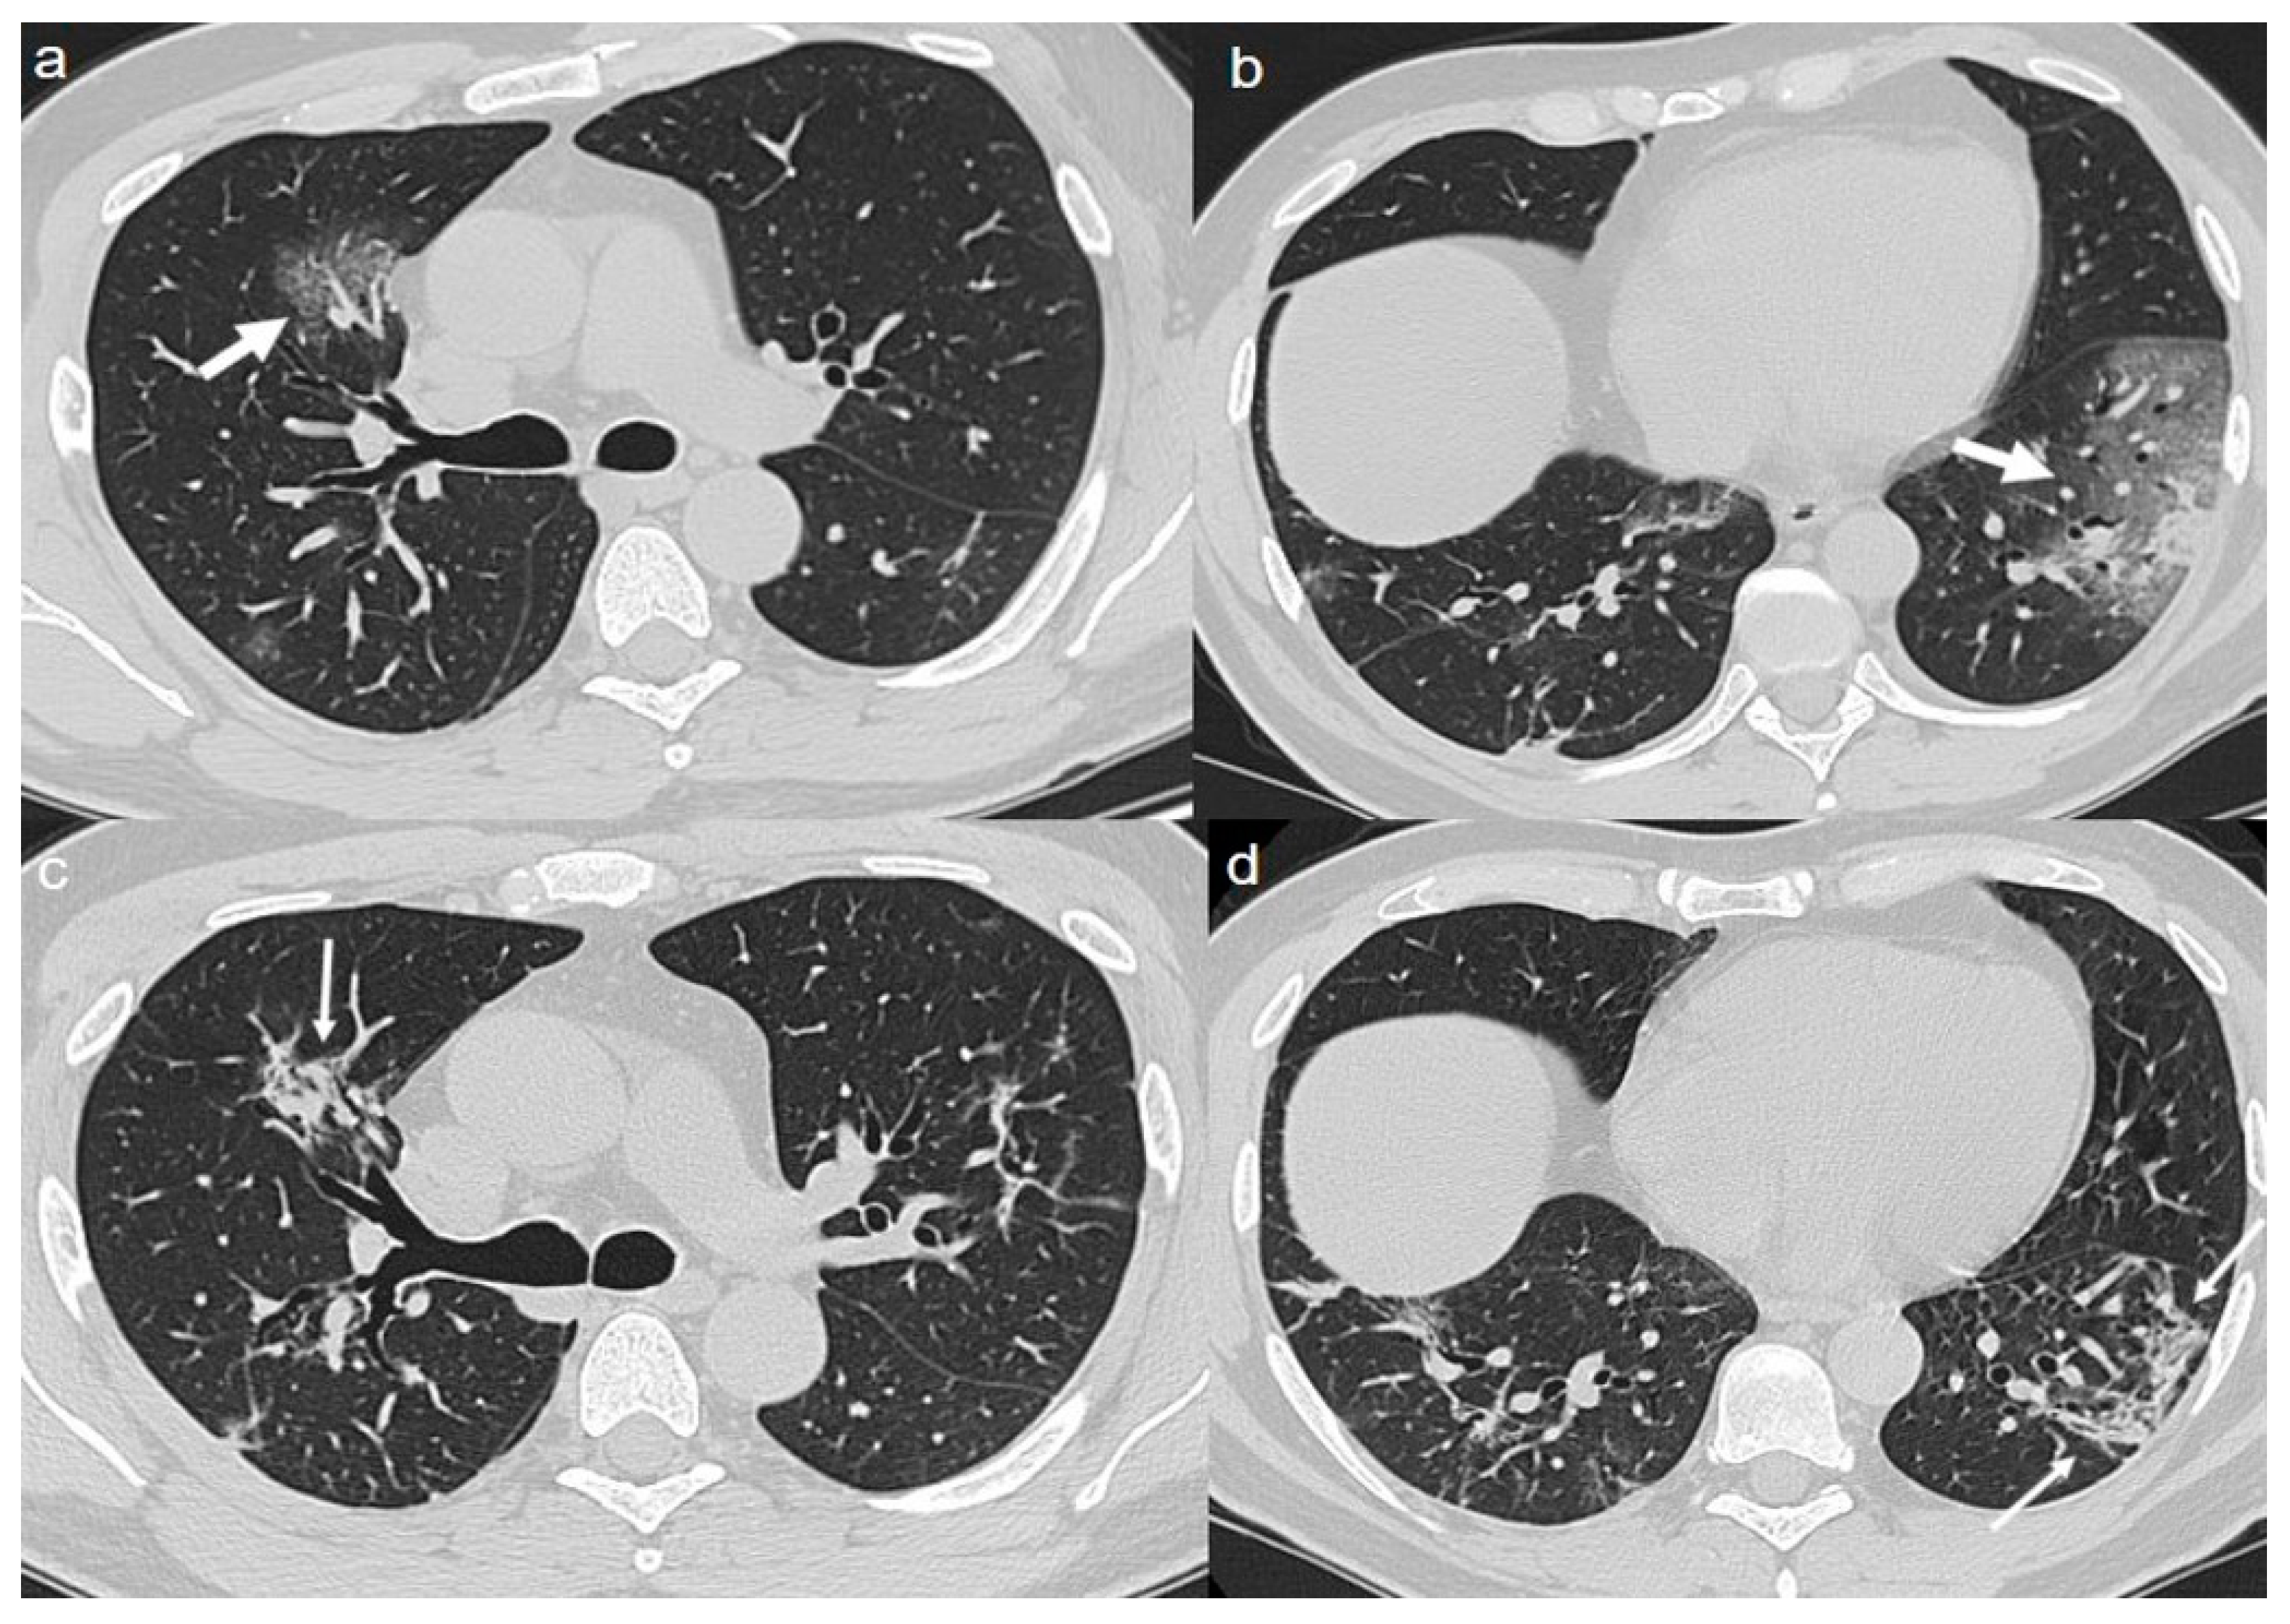

On admission, chest CT showed a diffuse “crazy paving pattern” peripherally located in the lower lobes (Figure 2a,b).

A chest CT at 4 months from the onset of symptoms showed the persistence of mixed pattern characterized by GGOs and fibrous streaks, bilaterally located. (Figure 2c,d).

Figure 2. (a,b) CT shows a “crazy paving pattern” peripherally located in lower lobes (arrows). (c,d) CT after 4 months from the onset of symptoms shows bilateral persistence of mixed pattern characterized by GGOs (thin arrows in c) and fibrous streaks (thin arrows in d).